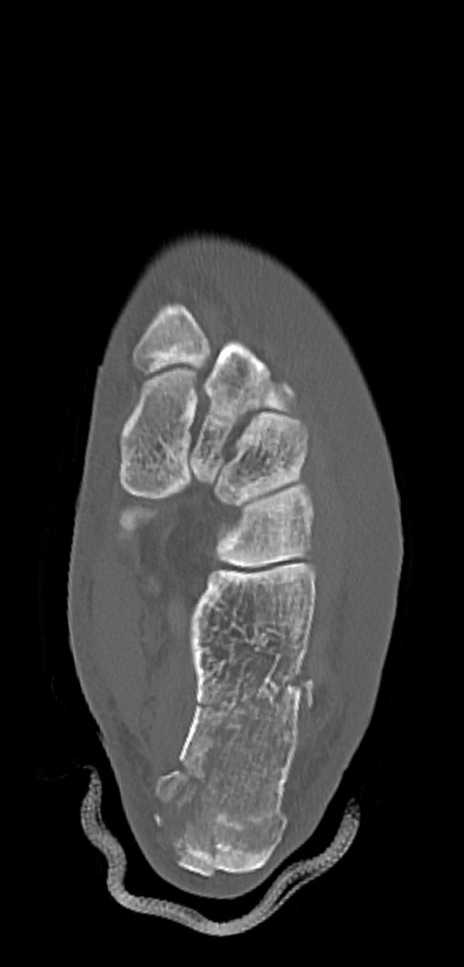

症例37 左足関節CT(横断像)

左足関節CT

矢状断像